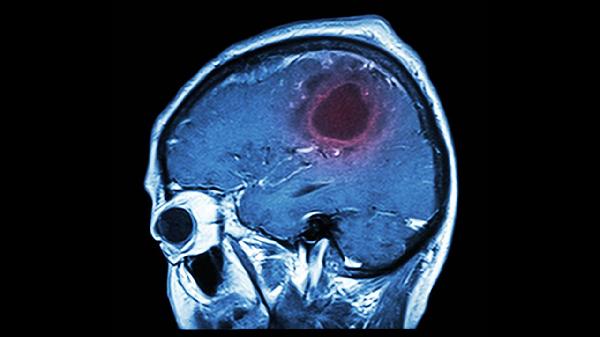

脑血栓后遗症的有哪些症状表现

脑血栓后遗症主要表现为肢体偏瘫、言语障碍、感觉异常、吞咽困难和认知功能下降等症状。脑血栓后遗症通常由脑组织缺血性坏死导致神经功能缺损引起,可能遗留长期功能障碍。

脑血栓后遗症患者需坚持长期康复训练,保持低盐低脂饮食,控制血压血糖在合理范围。家属应协助患者进行日常功能锻炼,定期复查头颅影像学检查。出现症状加重或新发功能障碍时需及时就医,避免自行调整药物剂量。